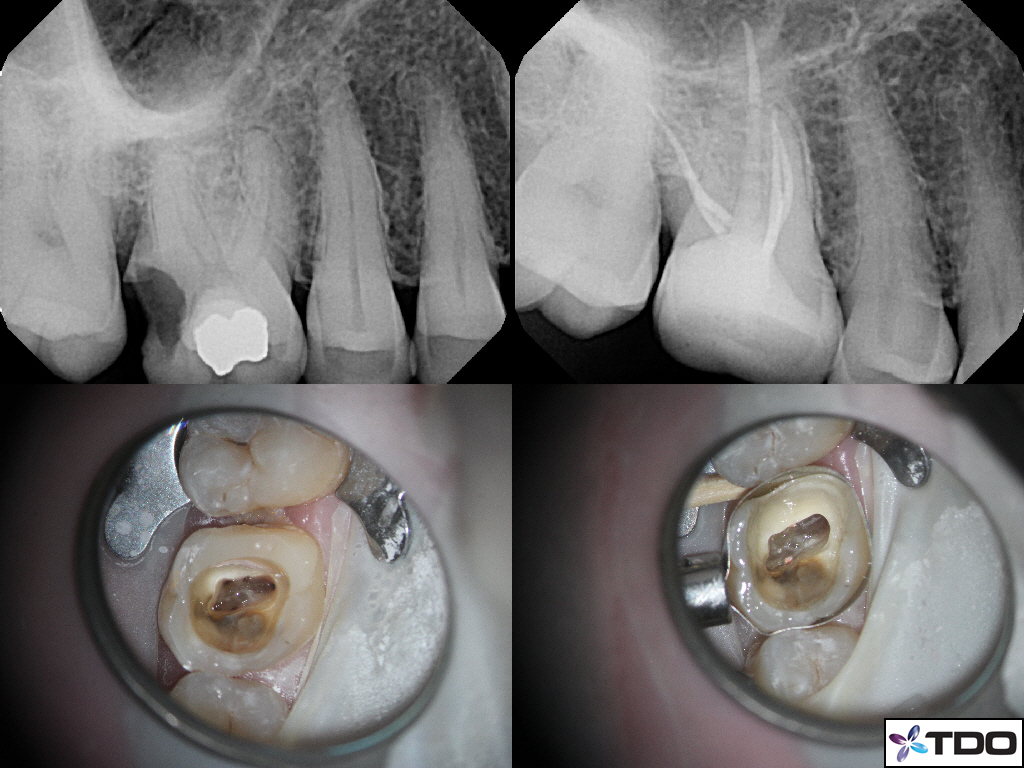

Spectacular Awe Inspiring!